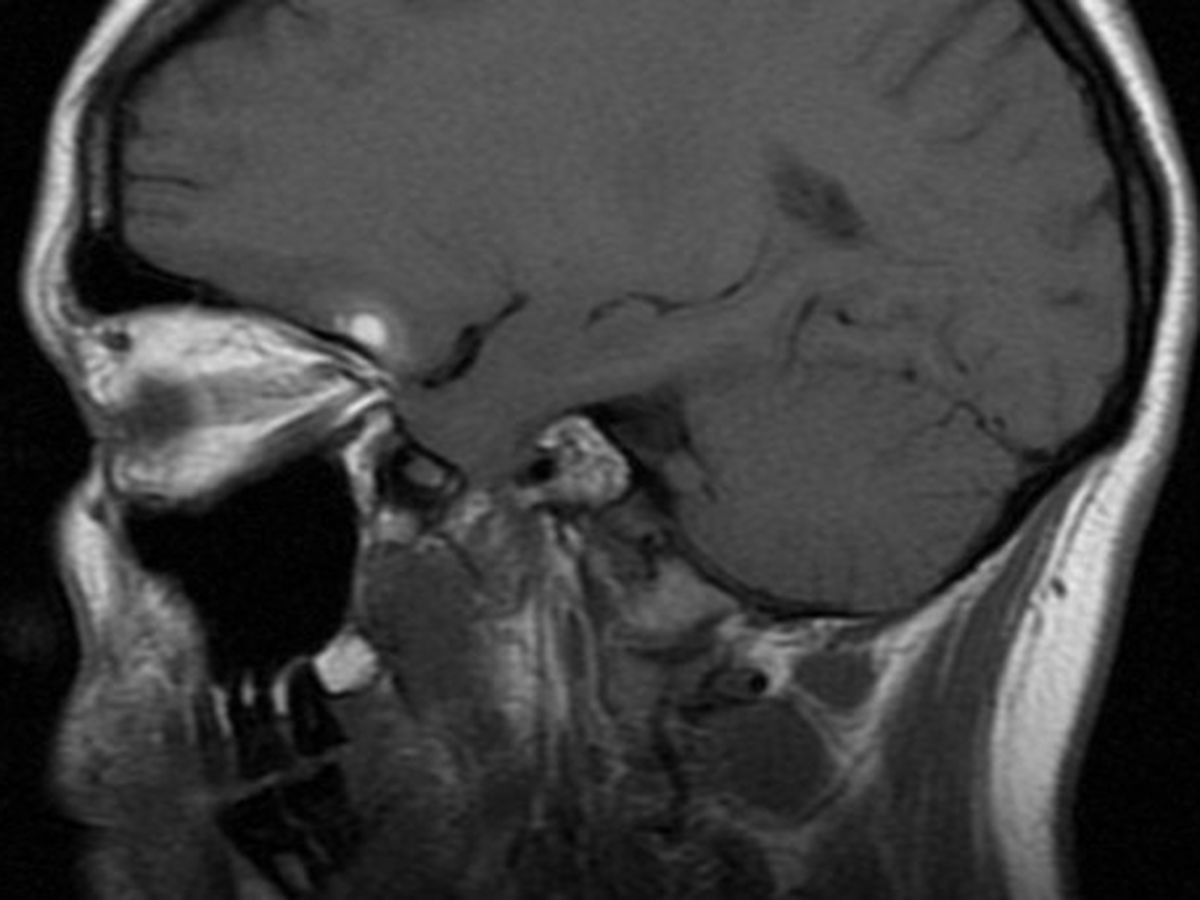

Join our campaign to help our friend, Emily DeCola! Not long ago, Emily was struck by a cyclist while crossing 2nd Ave. on her way to work. As her head hit the pavement, her marvelous grey matter jostled around, causing some brain bruising, a small hematoma, and injuring the delicate nerve between her nose and noggin, ending her sense of smell.Without a sense of smell, her sense of taste and her enjoyment of life have been flattened to a dull Salty, Bitter, Sweet, Sour experience of the world.